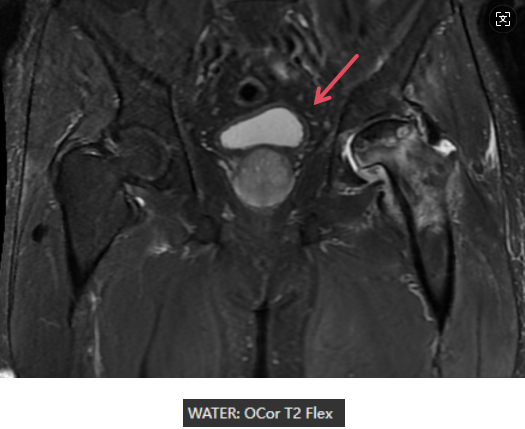

MR表现

左侧股骨头变扁,局部塌陷,骨质内见线状T1WI低信号,髋臼及股骨近端骨松质见片状T1WI低、T2WI压脂高信号,DWI高信号,周围滑膜增厚,邻近软组织肿胀,PD压脂信号增高,关节腔少量积液。